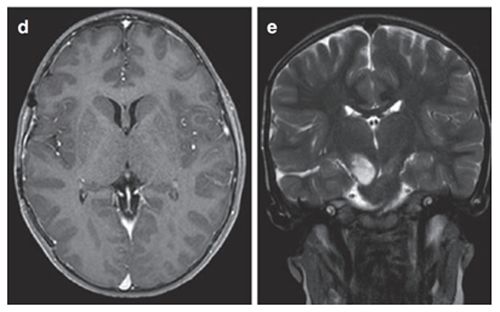

鲁特卡教授实施经颞中回-脑室入路次全切除术,病理证实为WHO I级毛细胞星形细胞瘤,BRAF重复融合、BRAF V600E及H3K27M检测均为阴性,基因检测检出NF1基因变异。术后影像学随访显示丘脑部分切除及中脑残留病灶,制定个体化辅助放疗方案,患儿治疗反应良好。术后6个月复查确认肿瘤控制稳定。